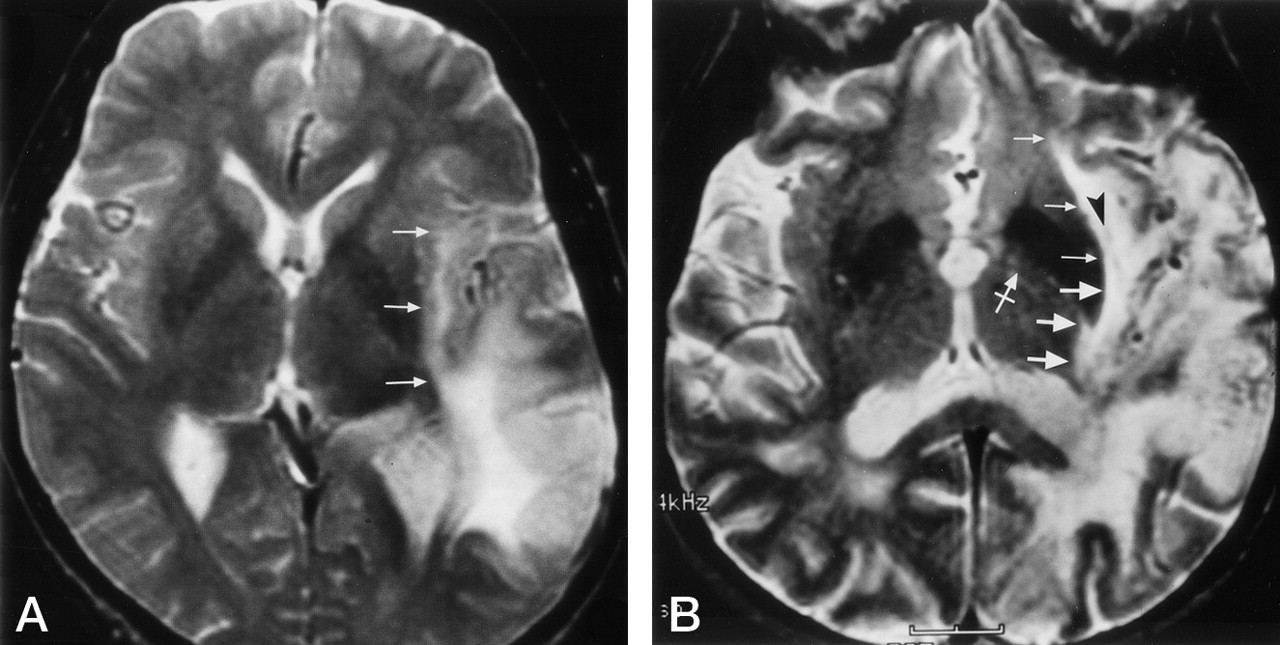

Clinical examples show involvement of the inferior occipitofrontal fasciculus at coronal MR planes corresponding to those in Figure 6.

A, Enhanced T1-weighted image in a 58-year old man with a recurrent glioblastoma multiforme. This image is at the level of the frontal horn of the lateral ventricle, and the amygdala (A). Comparison with Figure 6A demonstrates that the enhanced tumor is spreading out of the temporal lobe via the region of the uncinate fasciculus (large arrows). The nonenhanced edema and tumor in the extreme and external capsules, around the claustrum (arrowhead), involve the region of the inferior occipitofrontal fasciculus (small arrows). This combined involvement of the uncinate fasciculus and the inferior occipitofrontal fasciculus may vary depending on the exact location of the upper margin of the uncinate fasciculus and the lower margin of the inferior occipitofrontal fasciculus and the angulation of the section.

B, Proton density–weighted image in a 52-year-old man with a temporal lobe astrocytoma spreading into the extreme and external capsules at the posterior amygdala/hippocampal head level. Comparison with Figure 6B shows that the tumor and edema is spreading out of the temporal lobe via the region of both the uncinate fasciculus (large arrows) and the inferior occipitofrontal fasciculus (small arrows).

C, T2-weighted image in a 36-year-old woman with a temporal lobe astrocytoma spreading into the extreme and external capsules. The tumor is at the level of the body of the lateral ventricle and hippocampus. Comparison with Figure 6C, obtained at a similar coronal plane, demonstrates that the tumor and edema are spreading out of the temporal lobe via the region of the inferior occipitofrontal fasciculus (arrows).

D, T2-weighted image in a 68-year-old woman with a temporal lobe anaplastic oligodendroglioma spreading into the deep white matter lateral to the thalamus. Comparison with Figure 6D demonstrates that the inferior occipitofrontal fasciculus (arrows) is involved in the tumor and edema spread out of the temporal lobe.

Corresponding clinical examples involving the inferior occipital fasciculus in the axial plane.

A, In this 41-year-old woman, the tumor has spread to the extreme capsule. Comparison with Figure 7A shows that, at the level of the lateral ventricle, the tumor and edema is spreading out of the temporal lobe via the region of the inferior occipitofrontal fasciculus (arrows).

B, In this 61-year-old man, the tumor has spread into the extreme and external capsules around the claustrum (arrowhead). This image is at the level of the third ventricle and the anterior commissure (crossed arrow). Locations of the inferior occipitofrontal fasciculus and the uncinate fasciculus in Figure 7B and C suggest that the tumor and edema has spread out of the temporal lobe via the region of both the inferior occipitofrontal fasciculus (small arrows) and the uncinate fasciculus (large arrows). Depending on the angulation of the axial plane, or a few millimeters change in section selection, tumor spread at the anterior commissure level may involve the inferior occipitofrontal fasciculus and the uncinate fasciculus to a variable degree.